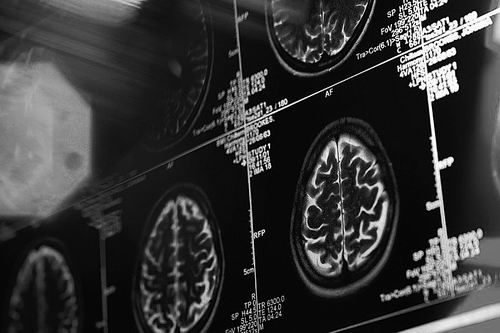

扫描大脑就能预测未来?

美国加利福尼亚州斯坦福大学的布莱恩·纳特森和他的团队召集了30位志愿者,让他们决定是否向某著名众筹网站的36个项目进行投资,并在他们抉择的时候用仪器扫描他们的大脑。

真正的众筹活动在几周后结束,其中18个项目获得了足够的资金。而在检视参与者的大脑扫描结果时,研究小组发现,当他们考虑这18个后来成功的项目时,大脑中一处被称为伏隔核的区域会出现不同的活动状态。

该小组采用一种算法通过扫描数据来识别脑活动的差异。在仅使用神经活动数据时,该算法能够预测哪些众筹项目将获得资助,其准确性达到59.1%。

另一方面,在考虑每个提案时,志愿者被要求评估他们对每个项目的喜欢程度,以及他们认为每个项目达到筹资目标的可能性。这些评分的预测结果只有52.9%的准确性,逊色于伏隔核区域活动所呈现的预测能力。

考虑到大脑的其他部分可能进一步增强脑扫描的预测能力,当纳特森的团队训练全脑神经活动的算法时,他们预测众筹结果的准确率能够达到67%。